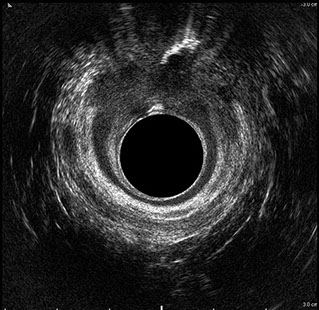

L’ecografia transanale è un esame diagnostico per immagini che consiste nell’introduzione di un trasduttore ad ultrasuoni. Le immagini qualitativamente migliori del canale anale sono ottenute usando un trasduttore rotante, montato in un manipolo rigido, che fornisce un’immagine a 360°. Con le apparecchiature più moderne è anche possibile ottenere immagini tridimensionali.

L’ecografia transanale permette di distinguere la sottomucosa che riveste il canale anale, lo sfintere anale interno, e lo sfintere anale esterno.